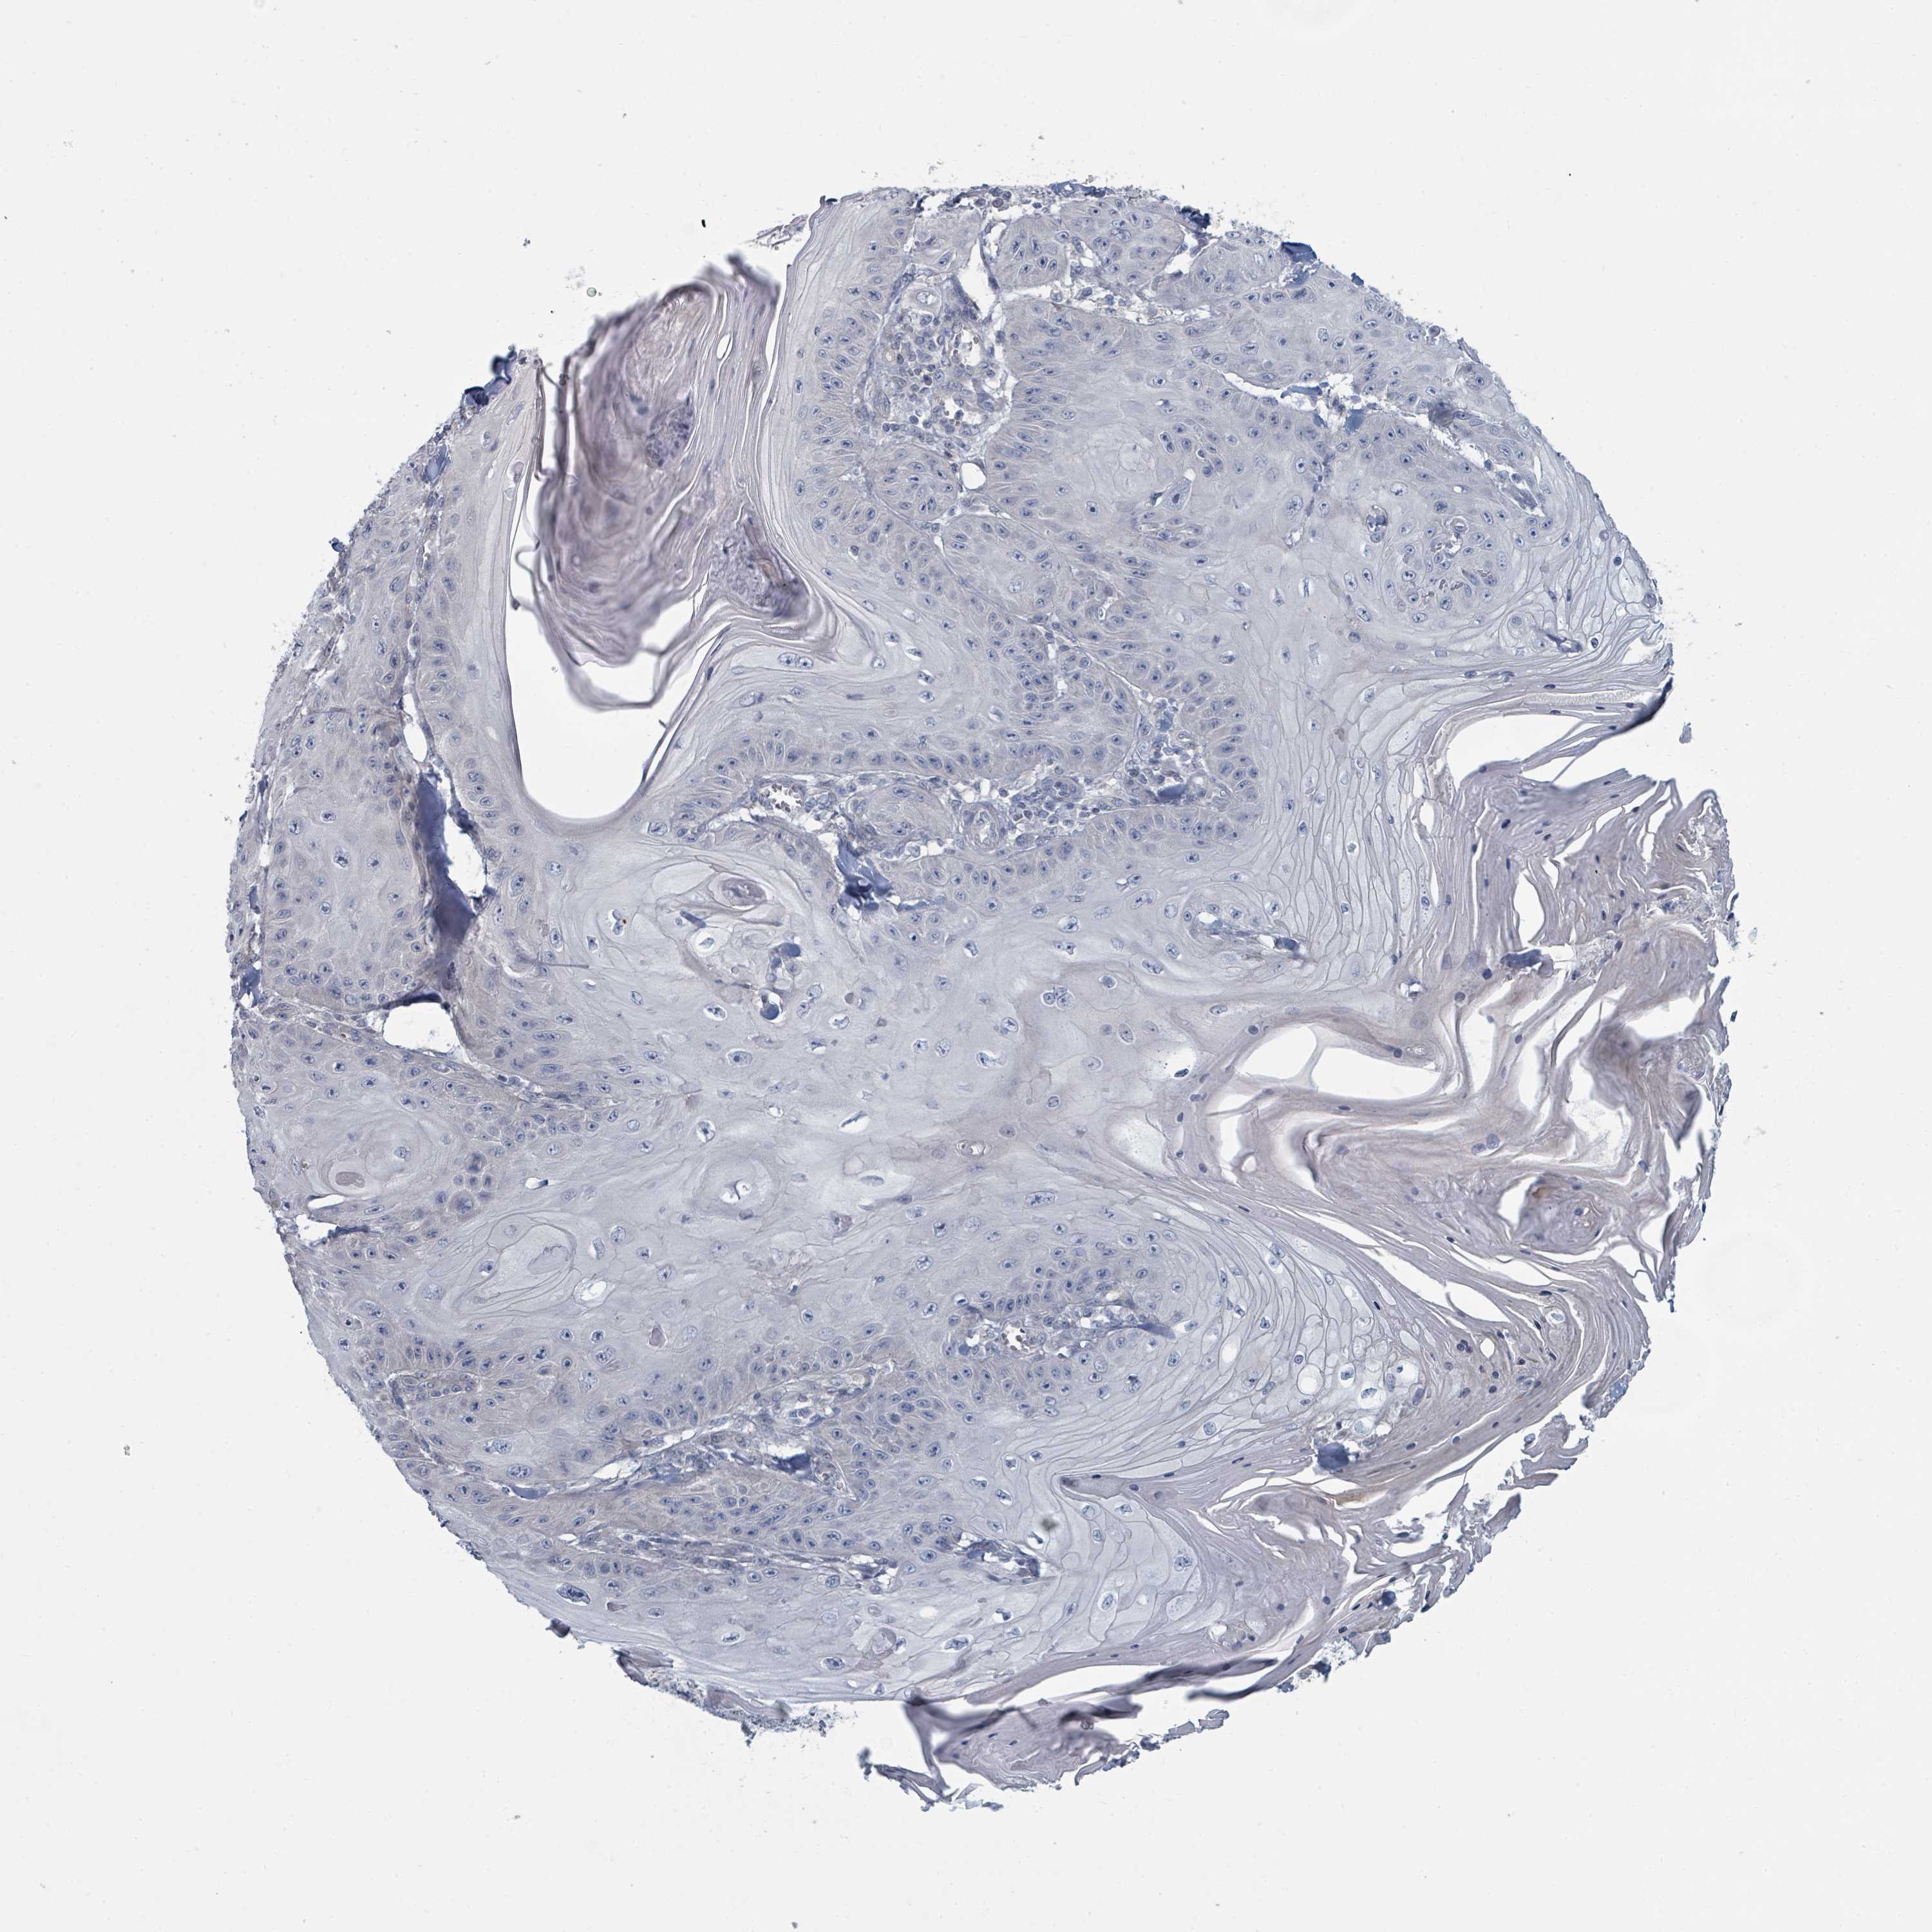

Basal cell and squamous cell cancer

SKIN CANCER - Protein expressioni

A mouse-over function shows sample information and annotation data. Click on an image to view it in a full screen mode. Samples can be filtered based on level of antibody staining by selecting one or several of the following categories: high, medium, low and not detected. The assay and annotation is described here.

Each image is clickable and will lead to virtual microscopy that enables deeper exploration of all samples and also displays staining intensity scores, fraction scores and subcellular localization as well as patient and tissue information for each sample.

Antibody HPA050821

Basal cell carcinoma